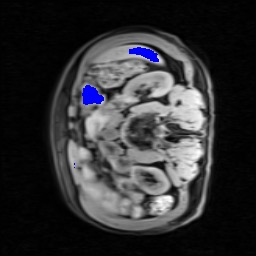

Transformers have made remarkable progress towards modeling long-range dependencies within the medical image analysis domain. However, current transformer-based models suffer from several disadvantages: (1) existing methods fail to capture the important features of the images due to the naive tokenization scheme; (2) the models suffer from information loss because they only consider single-scale feature representations; and (3) the segmentation label maps generated by the models are not accurate enough without considering rich semantic contexts and anatomical textures. In this work, we present CASTformer, a novel type of generative adversarial transformers, for 2D medical image segmentation. First, we take advantage of the pyramid structure to construct multi-scale representations and handle multi-scale variations. We then design a novel class-aware transformer module to better learn the discriminative regions of objects with semantic structures. Lastly, we utilize an adversarial training strategy that boosts segmentation accuracy and correspondingly allows a transformer-based discriminator to capture high-level semantically correlated contents and low-level anatomical features. Our experiments demonstrate that CASTformer dramatically outperforms previous state-of-the-art transformer-based approaches on three benchmarks, obtaining 2.54%-5.88% absolute improvements in Dice over previous models. Further qualitative experiments provide a more detailed picture of the model's inner workings, shed light on the challenges in improved transparency, and demonstrate that transfer learning can greatly improve performance and reduce the size of medical image datasets in training, making CASTformer a strong starting point for downstream medical image analysis tasks.